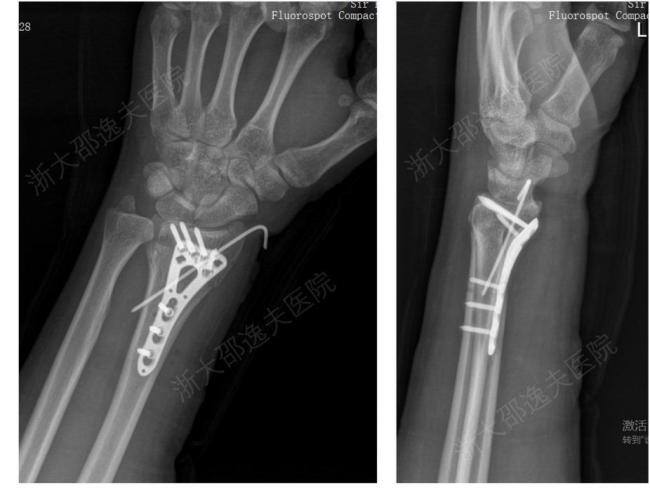

“骨02”在血液浸润的湿性生理环境下实现2-3分钟即时、强效黏合;操作简便高效,显著提升手术效率;材料可完全生物降解,约6个月后随骨愈合而自然吸收,实现真正的“无痕”,免除传统手术需二次手术之苦。“骨02”的临床价值已在全国各中心150余例受试病例中得到验证。例如,一位年轻工人因外伤导致腕部桡骨远端粉碎性骨折,应用“骨02”黏合技术,团队仅通过一个2-3厘米的微创切口注入“胶水”材料,短短3分钟内即完成了粉碎骨块的精准黏合与固定。术后3个月随访显示,患者骨折愈合良好,无并发症,腕关节功能完全恢复。